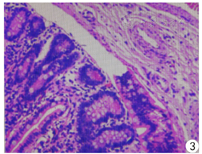

患儿,男,8岁,以"左侧腹股沟区不可复性肿物1 d余"为代主诉入院。1 d前家属发现患儿左侧腹股沟区出现一肿物,固定不能还纳,伴呕吐8次,非喷射性,为胃内容物,量较多,并伴腹痛、腹胀,无畏寒、发热,无腹泻、便秘,就诊于当地医院,考虑小肠梗阻,予以开塞露灌肠及输液等对症治疗,具体用药不详,症状无明显缓解,遂急诊转入院。入院后查体:患儿一般情况可,心、肺查体未见明显异常;腹膨隆,全腹轻压痛,无反跳痛;男性外阴;左侧腹股沟区触及一肿物,大小约3.5 cm×2.5 cm×2.5 cm,边界清,表面光滑,呈椭圆形,质韧,伴触痛,未坠入阴囊。用手将其向上进行挤压,不可还纳入腹腔,指压外环见外环口增宽。右侧腹股沟区未及肿物。双侧睾丸阴囊内未触及。血常规:白细胞计数(WBC)12.2×109/L,中性粒细胞百分率(NEUT) 49.3%。超声检查:①左侧腹股沟区可及一混合回声,大小约4.5 cm×1.8 cm×2.3 cm,边界清,其内为肠管回声,并可见一段异常肠袢,大小约2.5 cm×1.5 cm,壁增厚,回声减低,其一端与小肠相连,一端为盲端。此肿物向上延伸与腹腔相通,测疝径0.7 cm。见图1、图2。②双侧睾丸均位于腹股沟管,大小正常,轮廓规则,回声均匀。腹部DR平片:上腹部肠管胀气,并可见一长气液平面,中下腹部较密实,考虑肠梗阻。初步诊断为:1.左侧腹股沟嵌顿疝;2.不全性肠梗阻;3.双侧隐睾。遂于全身麻醉下行腹腔镜探查,术中见左侧腹股沟管内环口未闭,直径约0.8 cm,肠管位于内环口内,左侧睾丸位于左侧腹股沟管,可被牵拉入阴囊内,松手后睾丸回缩入腹股沟管内。右侧股沟股管内环口未闭,直径约0.5 cm,探查腹股沟管内环口远端约2.0 cm处可见睾丸回声,不能拉入阴囊内,向患儿家属告知病情后,暂不予以特殊处理。术中证实为左侧腹股沟嵌顿疝。腔镜直视下给予左侧腹股沟嵌顿疝复位,复位成功后见嵌顿肠管系膜对侧有一约1.5 cm×3.0 cm憩室,充血水肿,邻近肠管缺血坏死,长度约10.0 cm。首先于腔镜下常规行左侧疝囊高位结扎术,并沿脐窝下褶皱切口,用无损钳将憩室提出,处理回肠及憩室对应系膜,切除此段坏死肠管约10.0 cm及憩室,行端端吻合,全层间断缝合,浆肌层包埋,关闭系膜孔,逐层缝合切口。术后病理示:光镜下憩室内衬肠黏膜,肠壁及憩室淤血水肿、局部出血、少许炎细胞浸润(图3),考虑(回肠)Meckel憩室。术后患儿恢复良好,切口无明显疼痛,痊愈出院,术后1个月电话随访,状况良好,无特殊不适,疝无复发。

超声检查是诊断各种类型疝的首选检查方法,优于其他影像学检查,准确性和敏感性较高。高分辨力超声能明确疝内容物的性质,提示疝内肠壁有无水肿、穿孔,周围有无渗出、粘连等重要信息,利于临床选择合理的治疗方法。Littre疝超声表现有以下特点:①疝囊内可见一段异常肠袢,呈具有盲端的管状结构,一端与回肠相连;②疝囊内除异常肠袢外,可伴或不伴其他肠管;③异常肠袢位置固定,黏膜层、肌层及浆膜层不同程度的增厚,肠壁回声减低,边界模糊,考虑伴发憩室炎;④异常肠袢腔内张力减低,壁连续性中断,周围可见无回声液区,考虑伴发憩室穿孔。